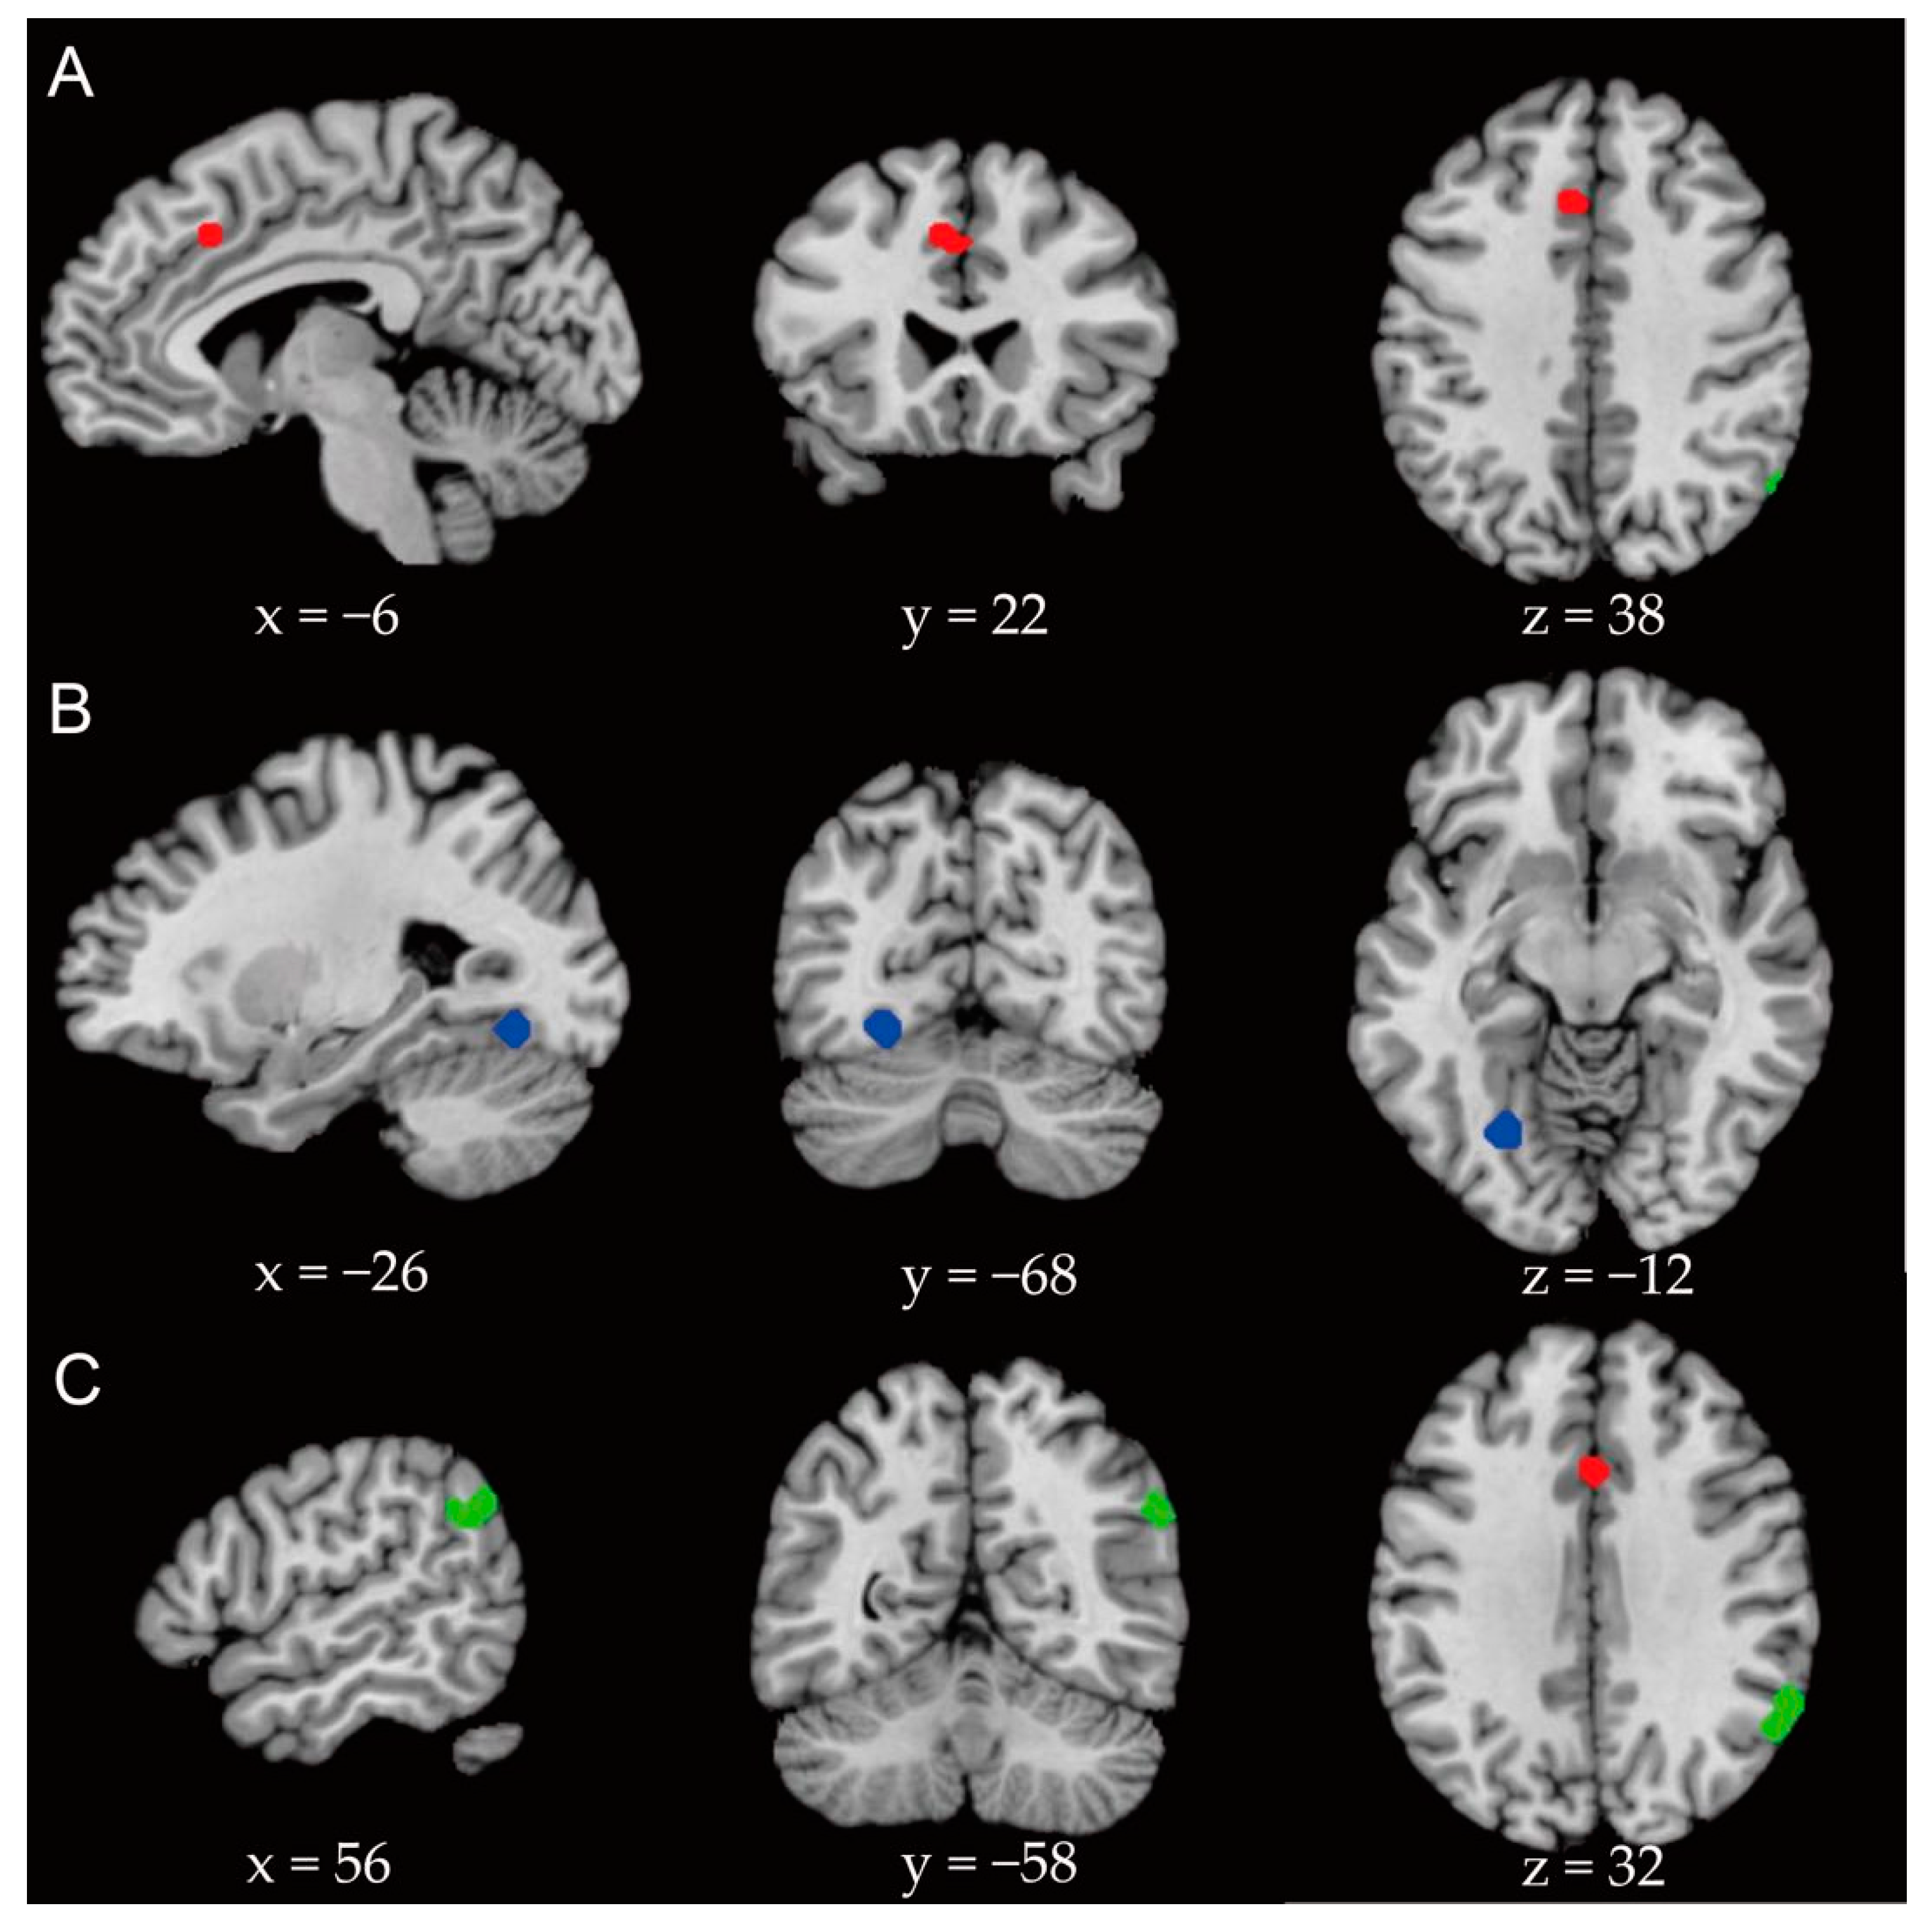

| Global analysis | −6 | 22 | 38 | 584 | 0.000124 | 0.015 | Anterior cingulate gyrus |

| Emotional face task | −26 | −68 | −12 | 496 | 0.00000034 | 0.015 | Cerebellar slope, fusiform gyrus |

| Situational task | 58 | −52 | 30 | 784 | 0.0000046 | 0.013 | Supramarginal gyrus and angular gyrus |